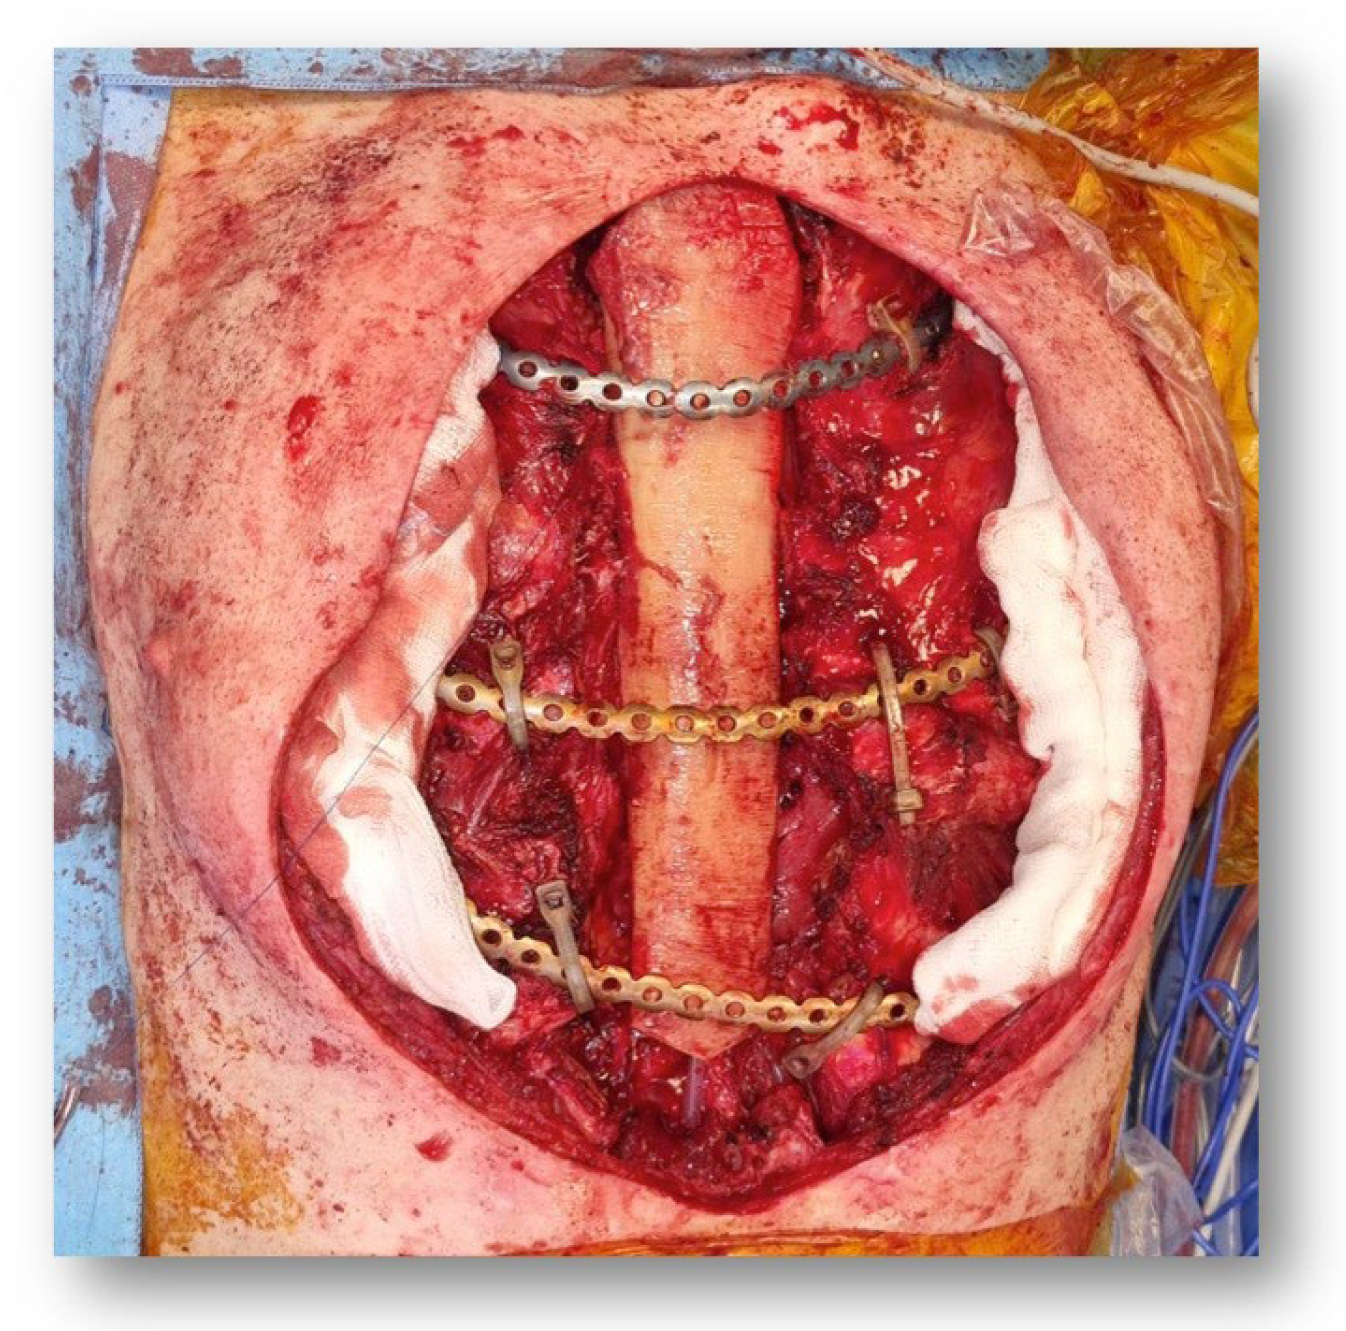

2. Case Report